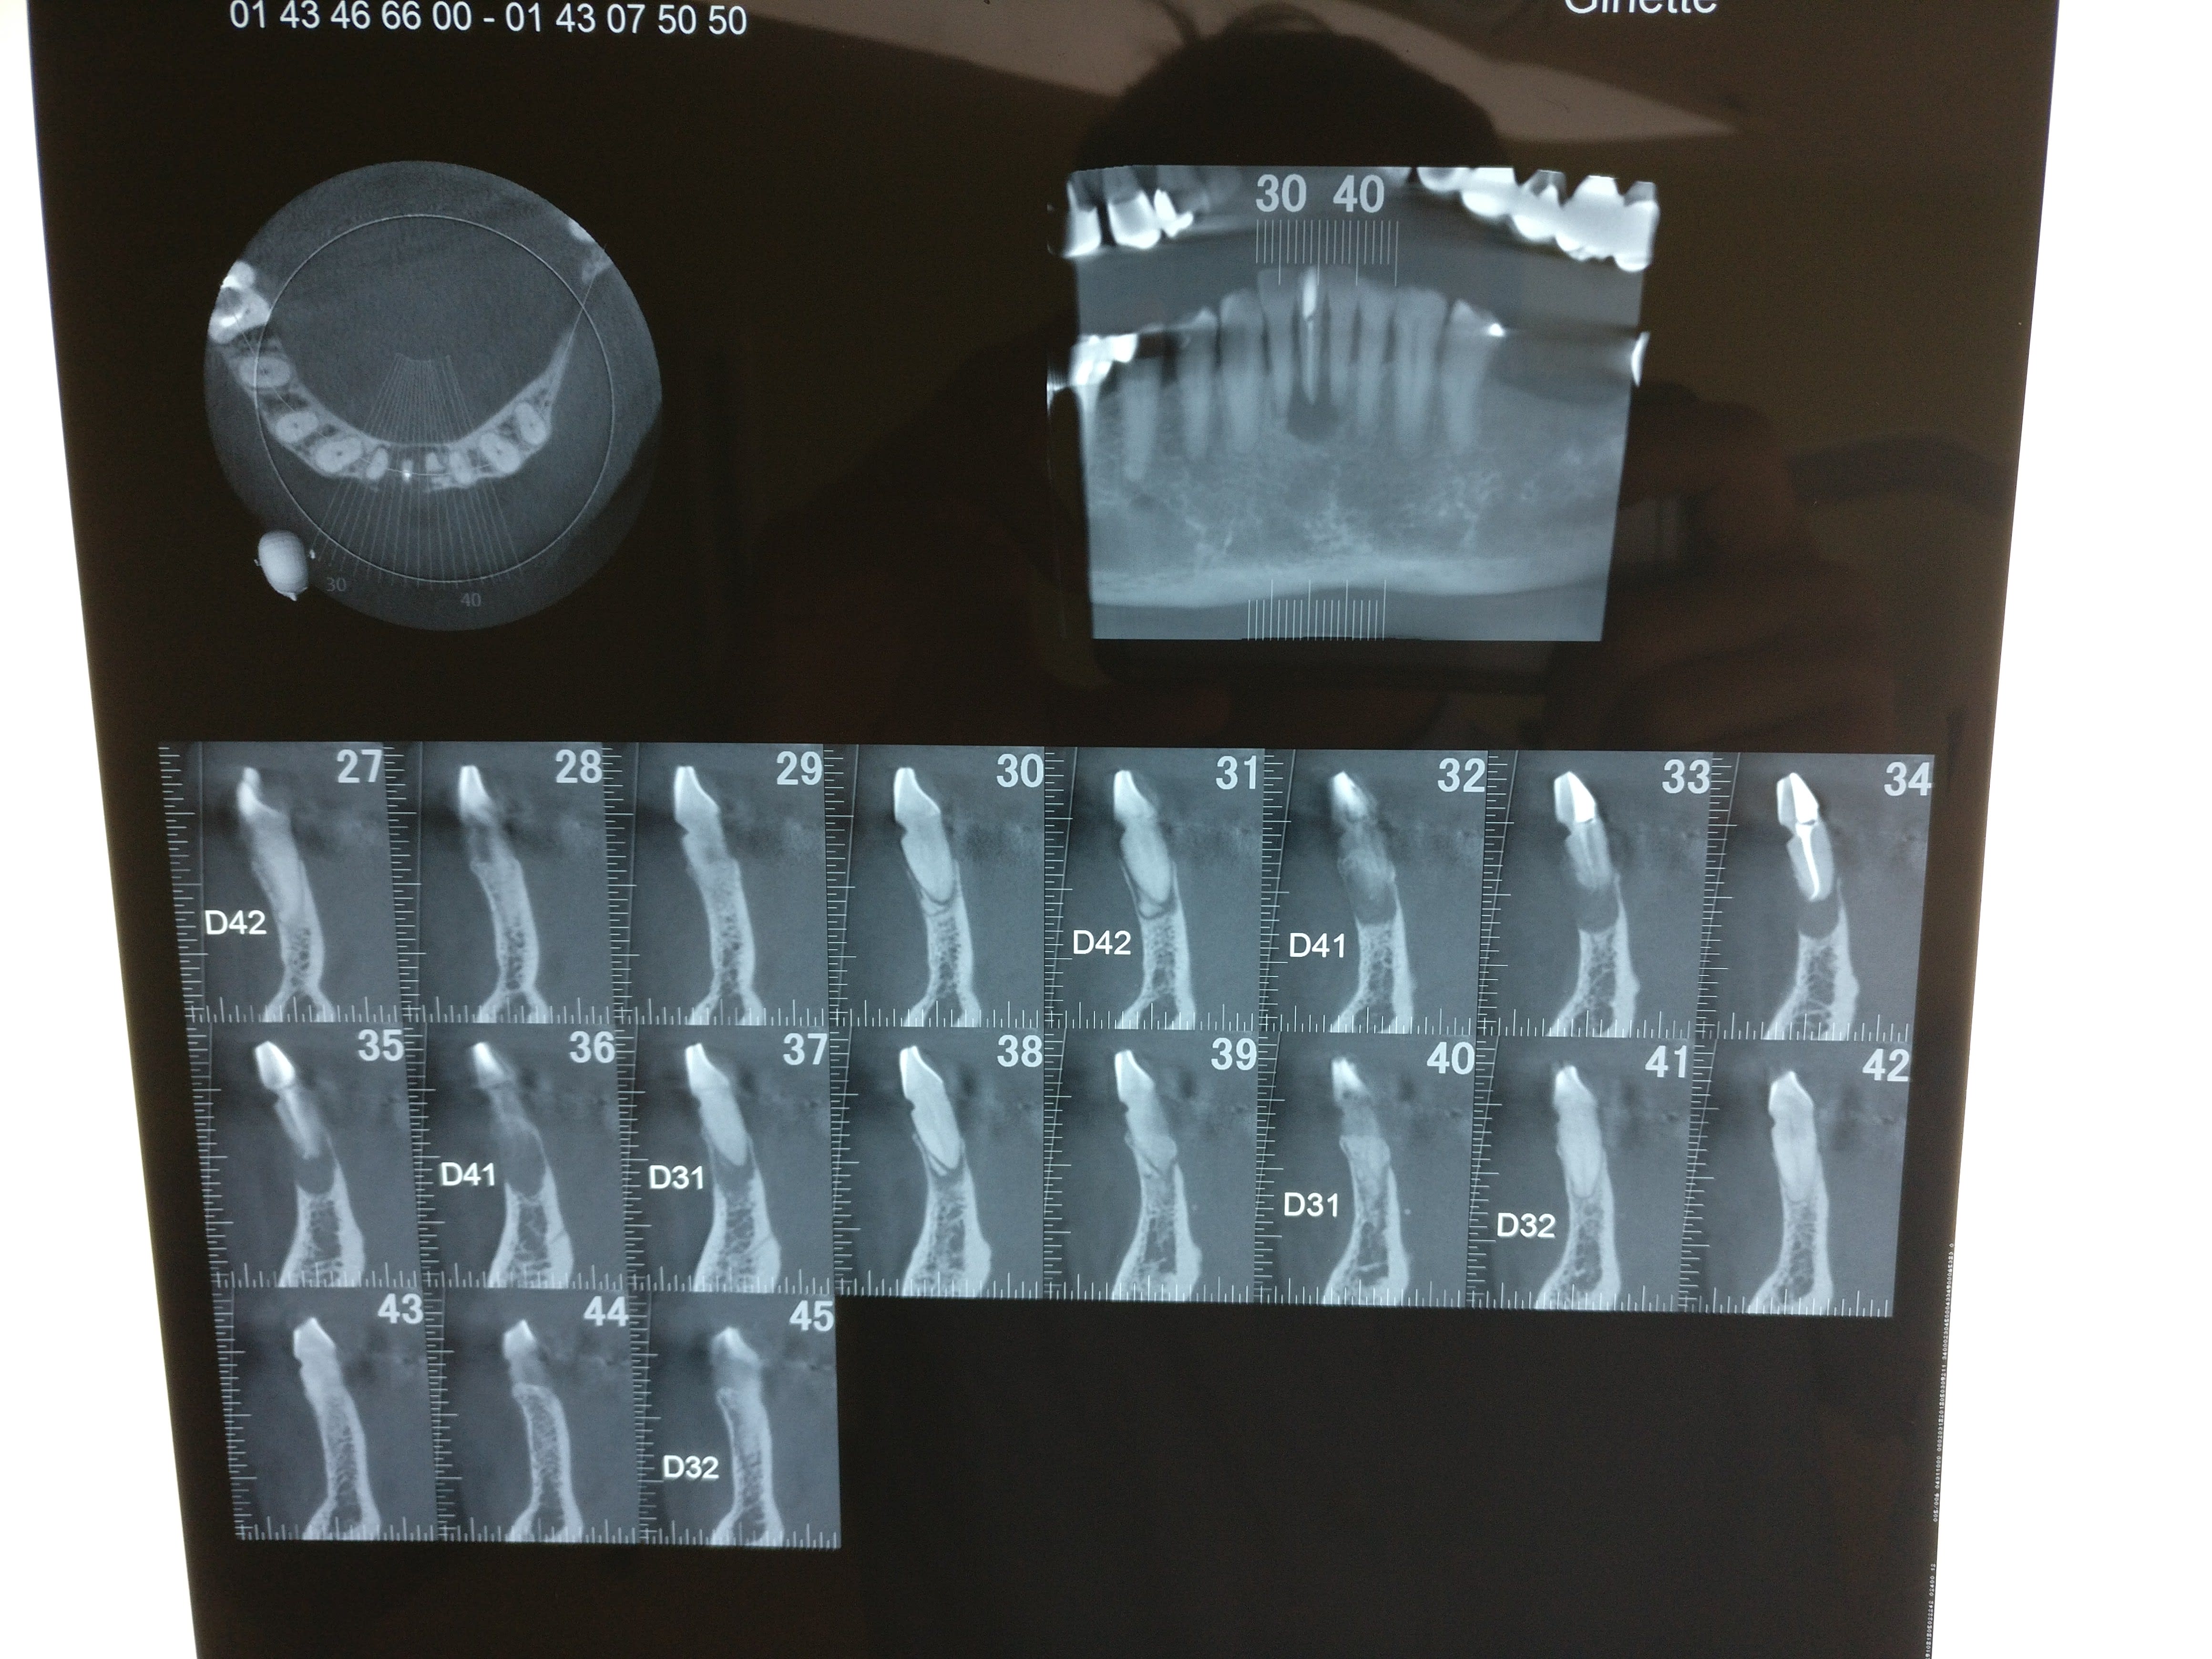

Mais surtout que pensez vous de ce qu'on voit sur les coupes 31 et 38? Morceaux de racines ? lors de l'exo faut les virer aussi? voir même extraire 41 et 32?

A la base je pense qu'il y avait un second canal en lingual. Regarde les coupes horizontales tu devrais le trouver ou au moins l'imaginer. Sur les coupes sagittales, le canal que tu as obture est deporte en vestibulaire, c'est une bonne indication. Sur la retro tu vois bien les deux racines de l'incisive latérale, tu trouves en general 2 canaux sur la centrale dans ce cas la.

Les images que tu vois en apical des voisines, je ne sais pas ce que c'est, mais je ne pense pas a des bouts de racines, plutot des bouts d'os en voie de sequestration (possible syndrome de Stockholm en vue).

Je vois de plus en plus souvent des incisives et canines mandibulaires avec 2 racines (encore une 33 traitée il y a 15 jours avec 2 racines chez une dame de 82 ans, chez qui j'ai précédemment retraitées les 42 et 32 à 2 racines avec infection apicale aujourd'hui totalement rentrés dans l'ordre).